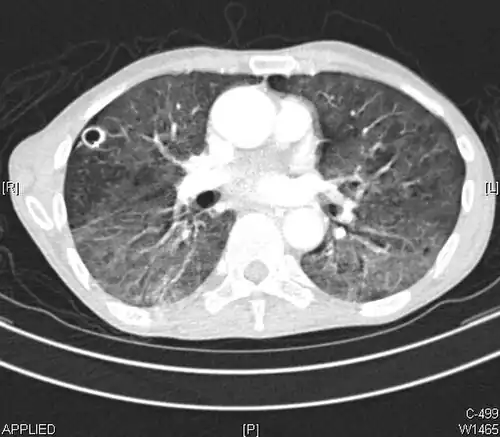

CT image showing patchy areas of ground-glass opacities representing pulmonary edema.

The diffuse pattern typically refers to GGOs in multiple lobes of one or both lungs. Broadly, a diffuse pattern of GGO can be caused by displacement of air with fluid, inflammatory debris, or fibrosis. Cardiogenic pulmonary edema and ARDS are common causes of a fluid-filled lung. Diffuse alveolar hemorrhage is a rarer cause of diffuse GGO seen in some types of vasculitis, autoimmune conditions, and bleeding disorders.[6]